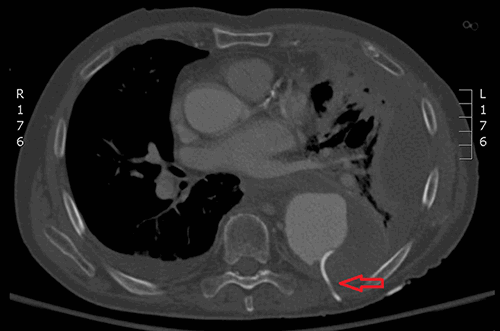

The patient was taken to the hybrid operating room for catheter removal and possible endovascular aneurysm repair. Notably, he was becoming hypotensive prior to entering the operating room, with blood pressures decreasing from the 130/80s range to 100/50s range during induction of anesthesia; small boluses of phenylephrine, norepinephrine, and 500ml of albumin bolus were required to maintain blood pressures of 100/50. The patient was positioned supine with the left chest bumped up into semi-decubitus position to allow visualization of the catheter as it exited the posterolateral chest. At this time, the patient became hypotensive again to 80/40. The left chest, abdomen, and bilateral groins were prepped into the sterile field. With ultrasound guidance, the right common femoral artery was accessed and a 5-French sheath placed. Over a guidewire, a pigtail catheter was advanced into the aortic arch. An aortogram (Figure 4) was obtained and ruled out aortic rupture as the cause of the hypotension.

Figure 4: intraoperative aortogram demonstrating aneurysmal degeneration of the thoracic aorta without evidence of rupture